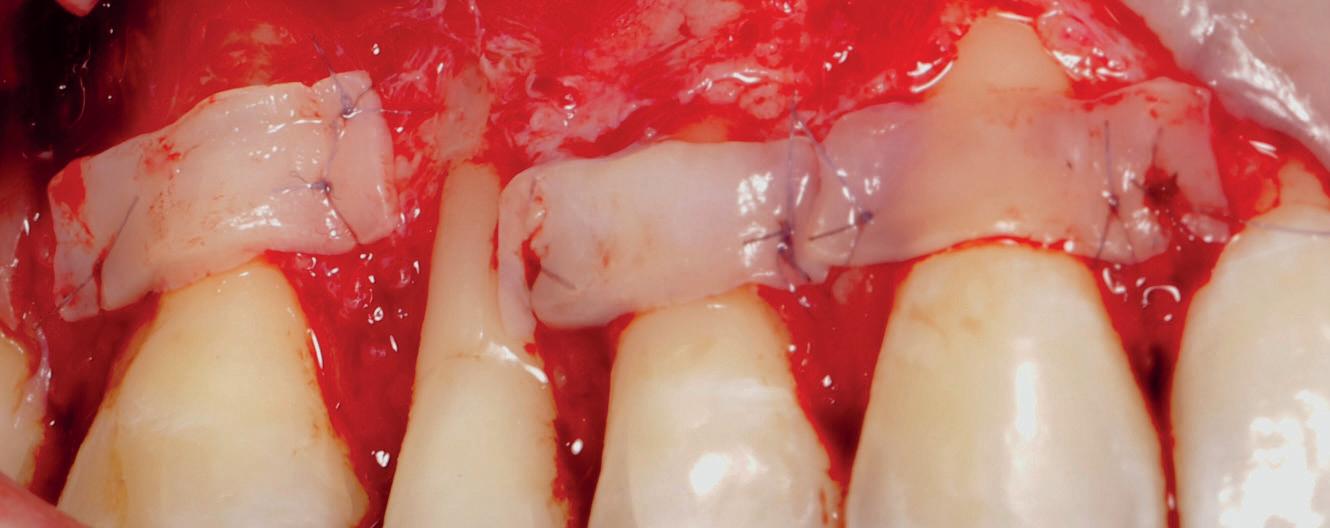

EthOss® is a 100% synthetic bone graft material for dental implant surgery. With no risk of cross-contamination, EthOss® works with the body’s healing process by creating a calciumrich environment and is completely absorbed.